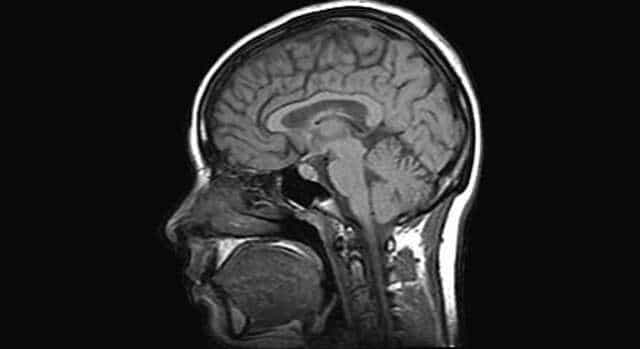

Un grupo de científicos de la compañía médica británica Heptares Therapeutics ha utilizado una de las máquinas de rayos X más potentes del mundo para estudiar la glándula pituitaria, situada en el cerebro, encargada de controlar el estrés la ansiedad e incluso la depresión.

Los científicos ya sabían que la glándula pituitaria jugaba un papel fundamental en los fenómenos de ansiedad y depresión, mediante la liberación de sustancias químicas a la sangre. Lo que no sabían era que la verdadera responsable de esta perturbacionesera la proteina CRF1, situada en las membranas externas de las células de la glándula.